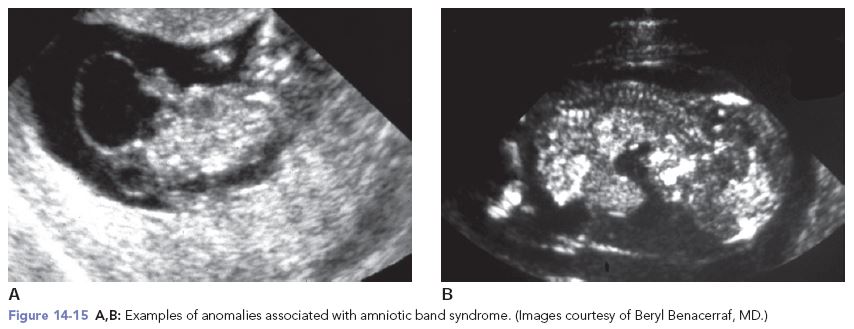

Amniotic band syndrome, also known as constriction ring syndrome, happens when fibrous bands of the amniotic sac (the lining inside the uterus that contains a fetus) get tangled around a developing fetus.

In rare cases, the bands wrap around the fetus’ head or umbilical cord. Most of the time, the bands wrap around an arm, leg, fingers, or toes. This can cause serious constrictions (tightening), acting like a tight rubber band around the body part. Most children with amniotic band syndrome will have bands on more than one part of the body.

Amniotic band syndrome is sometimes diagnosed before birth with an ultrasound test. Most of the time, it is seen when a baby is born. Your child may have an x-ray to help find out how serious the problem is.